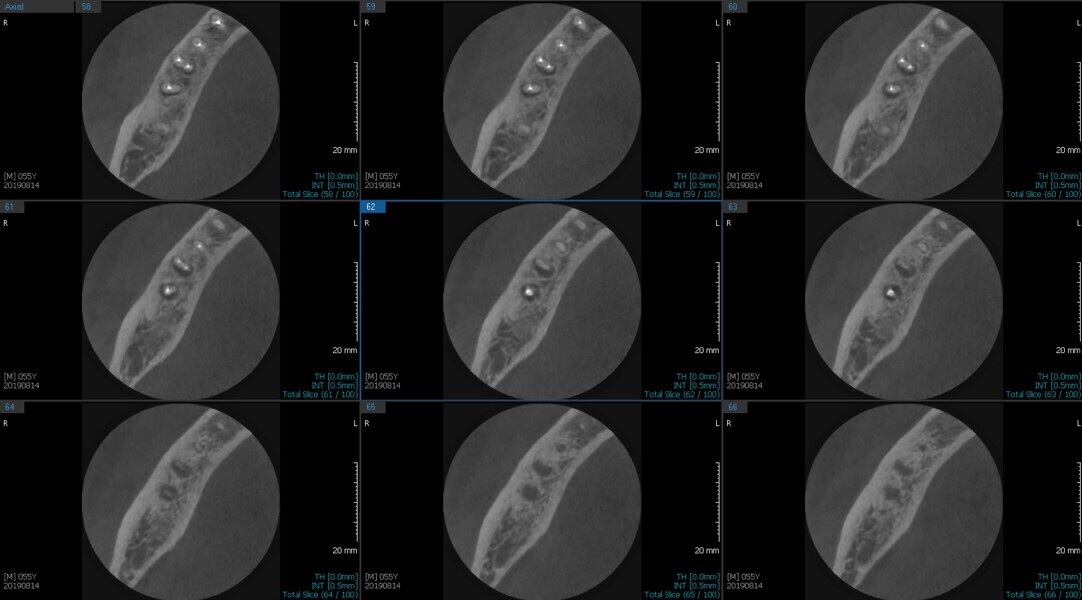

Fig.2a: Pre-op CBCT images of tooth #46: No obturation material in the distal and mesiobuccal canal (a); scanty obturation of the canals and breach of the floor of the pulp chamber, no obturation beyond a few millimetres down the orifice (b & c); radiolucency in the furcation area and periapical region of both roots (d -g).

Fig.2b: Pre-op CBCT images of tooth #46: No obturation material in the distal and mesiobuccal canal (a); scanty obturation of the canals and breach of the floor of the pulp chamber, no obturation beyond a few millimetres down the orifice (b & c); radiolucency in the furcation area and periapical region of both roots (d -g).

Fig.2c: Pre-op CBCT images of tooth #46: No obturation material in the distal and mesiobuccal canal (a); scanty obturation of the canals and breach of the floor of the pulp chamber, no obturation beyond a few millimetres down the orifice (b & c); radiolucency in the furcation area and periapical region of both roots (d -g).

Fig.2d: Pre-op CBCT images of tooth #46: No obturation material in the distal and mesiobuccal canal (a); scanty obturation of the canals and breach of the floor of the pulp chamber, no obturation beyond a few millimetres down the orifice (b & c); radiolucency in the furcation area and periapical region of both roots (d -g).

Fig.2e: Pre-op CBCT images of tooth #46: No obturation material in the distal and mesiobuccal canal (a); scanty obturation of the canals and breach of the floor of the pulp chamber, no obturation beyond a few millimetres down the orifice (b & c); radiolucency in the furcation area and periapical region of both roots (d -g).

Fig.2f: Pre-op CBCT images of tooth #46: No obturation material in the distal and mesiobuccal canal (a); scanty obturation of the canals and breach of the floor of the pulp chamber, no obturation beyond a few millimetres down the orifice (b & c); radiolucency in the furcation area and periapical region of both roots (d -g).

Fig.2g: Pre-op CBCT images of tooth #46: No obturation material in the distal and mesiobuccal canal (a); scanty obturation of the canals and breach of the floor of the pulp chamber, no obturation beyond a few millimetres down the orifice (b & c); radiolucency in the furcation area and periapical region of both roots (d -g).